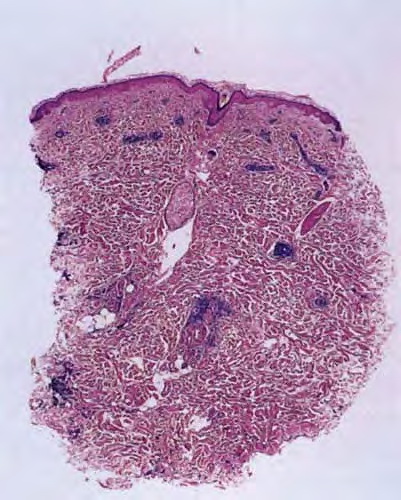

Erythema Chronicum Migrans =الحمامى المزمنة الهاجرة